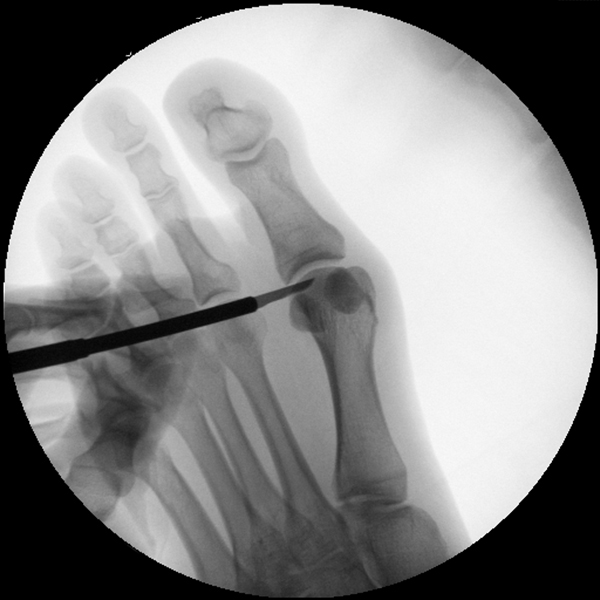

• Positionierung des Bildwandlers: 90° Winkel zum Os metatarsale I. Benötigt wird die Durchleuchtung des Vorfußes a.p., seitlich und schräg.

Operationstechnik

Der von Isham/Reverdin beschriebenen minimal invasiven Technik zur Korrektur einer Hallux valgus Deformität liegen 4 Operationsschritte zu Grunde:

3. Laterales Release

4. Akin Osteotomie der Großzehengrundphalanx

Die Folge der Operationsschritte sollte strikt von 1. - 4. erfolgen, da ansonsten die mediale Closing Wedge Osteotomie bei vorzeitigem lateralem Release und/oder Akin Osteotomie nicht geschlossen werden kann. Nach der von Isham beschriebenen Originaltechnik finden Implantate keine Anwendung, zur Sicherung und besseren Fixation können osteosynthetische Verfahren angewandt werden (siehe auch Fehler, Gefahren und Komplikationen).